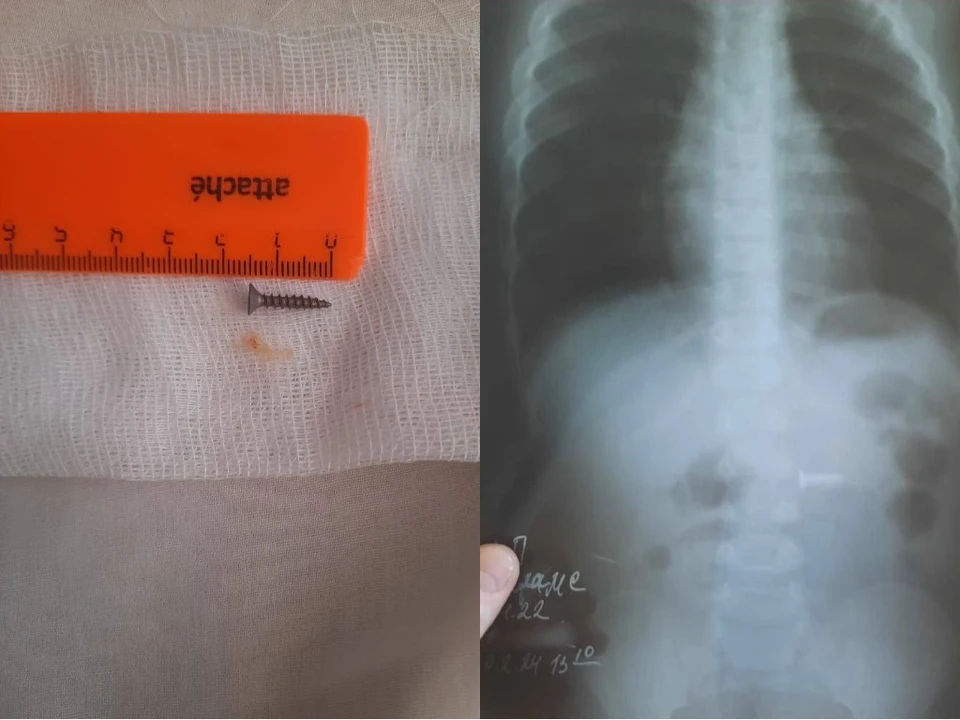

Проглотил болтик

Проглотил болтик 106 фотографий